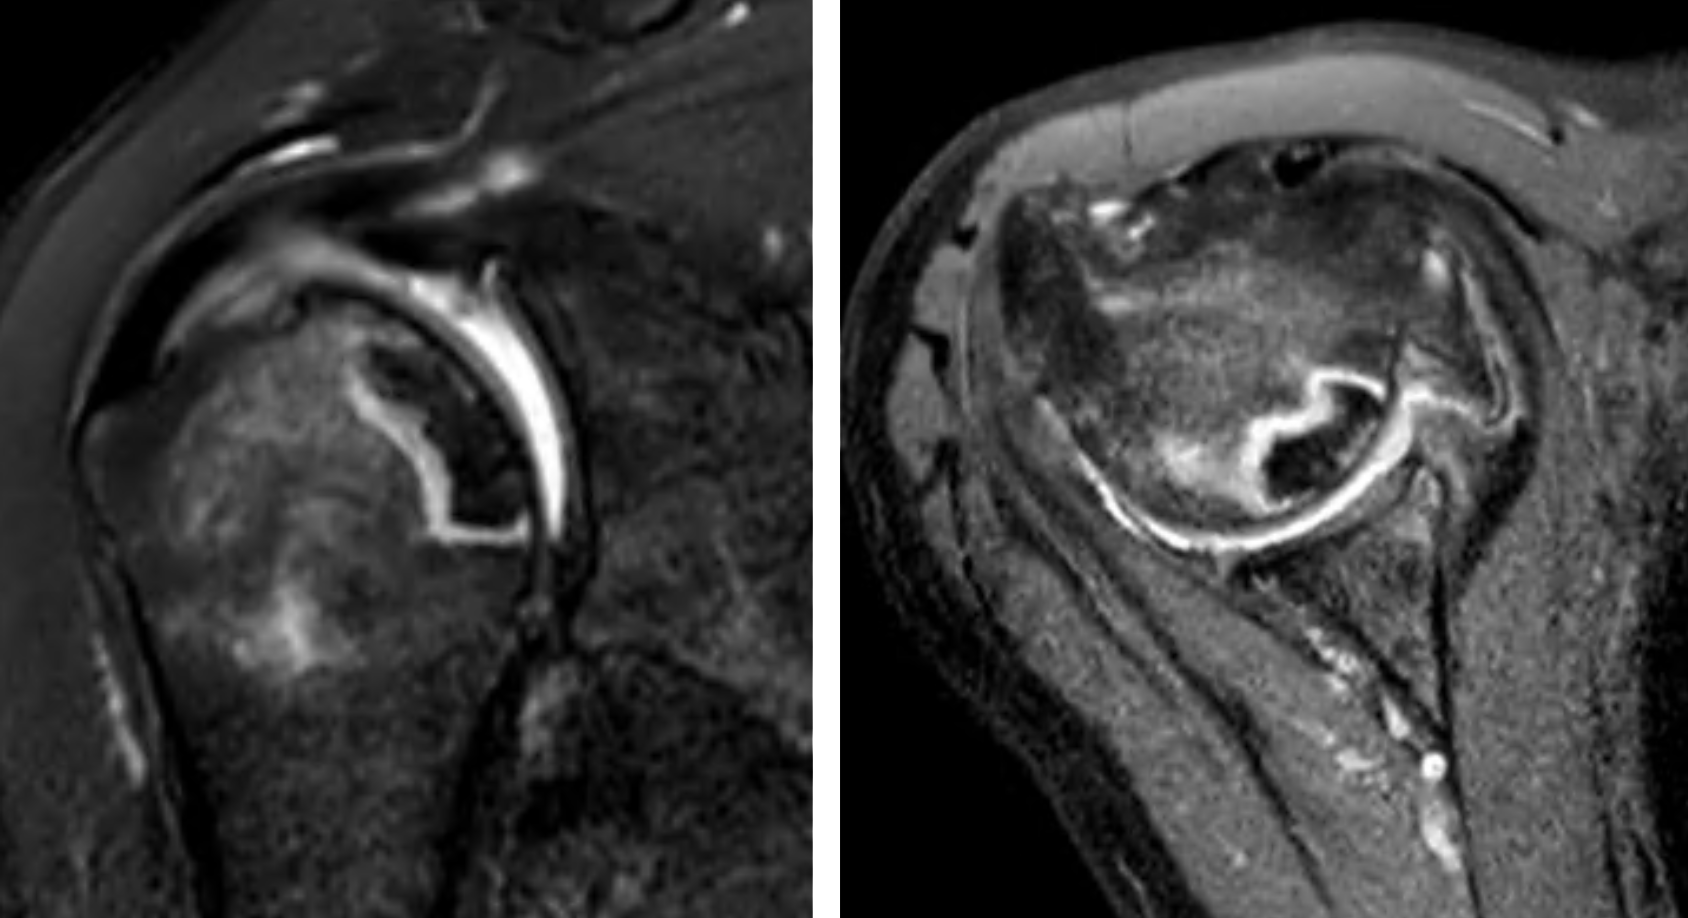

MRI scan showed preserved rotator cuff